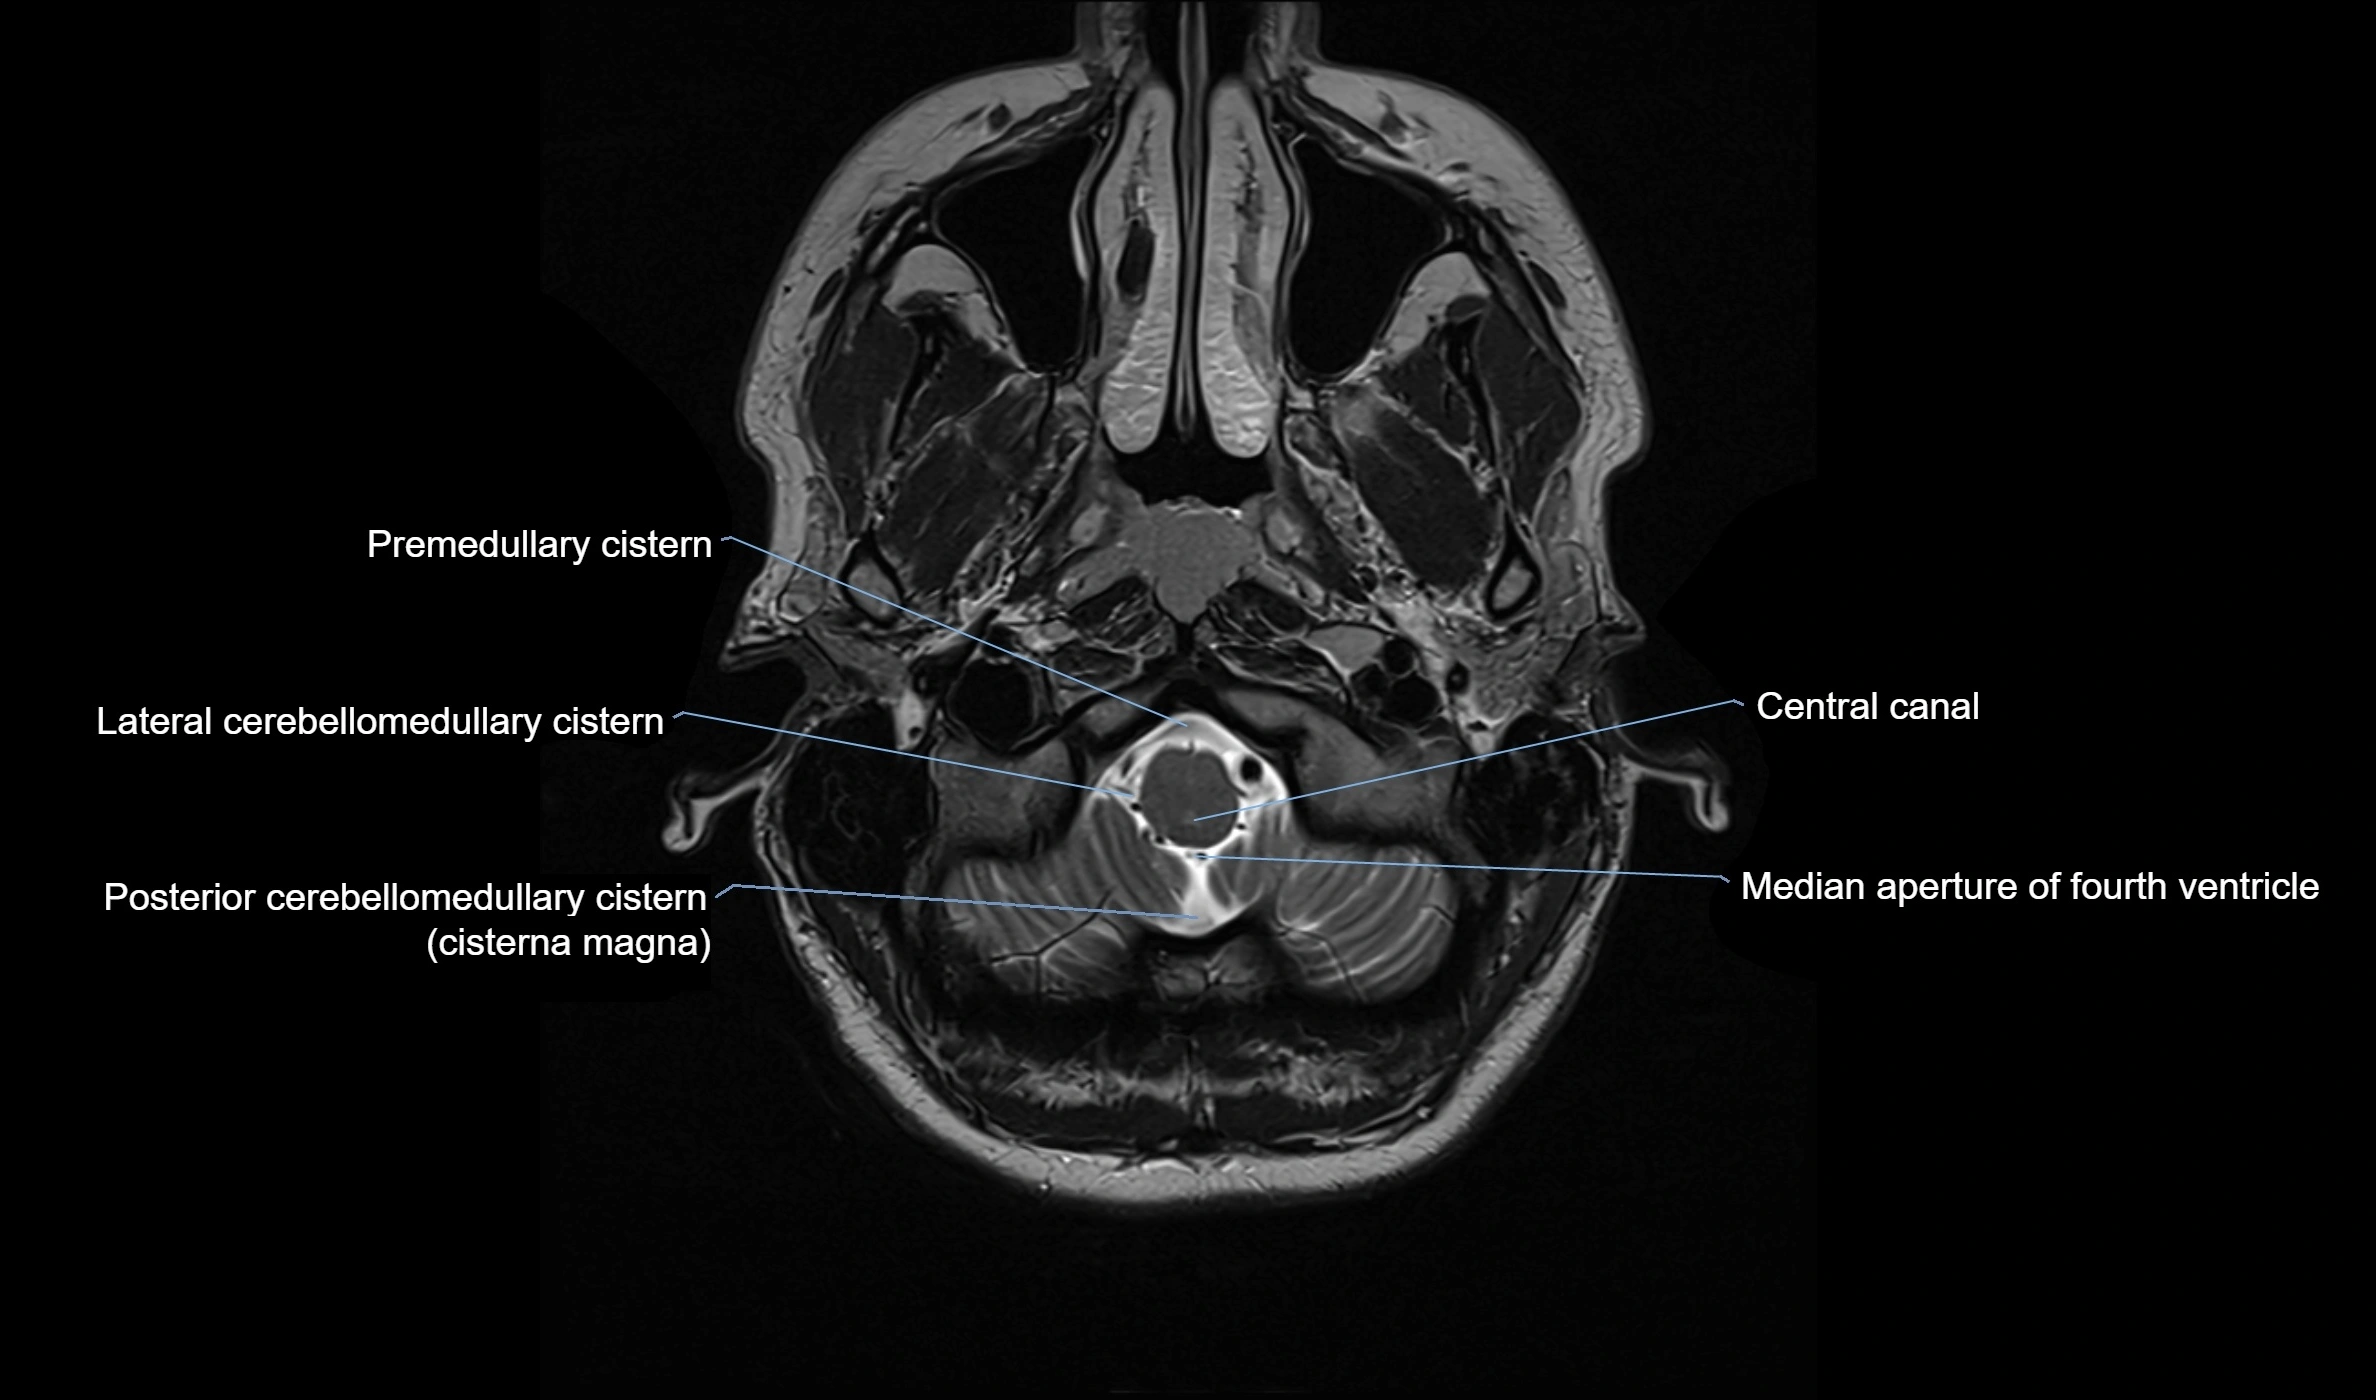

MRI images

image